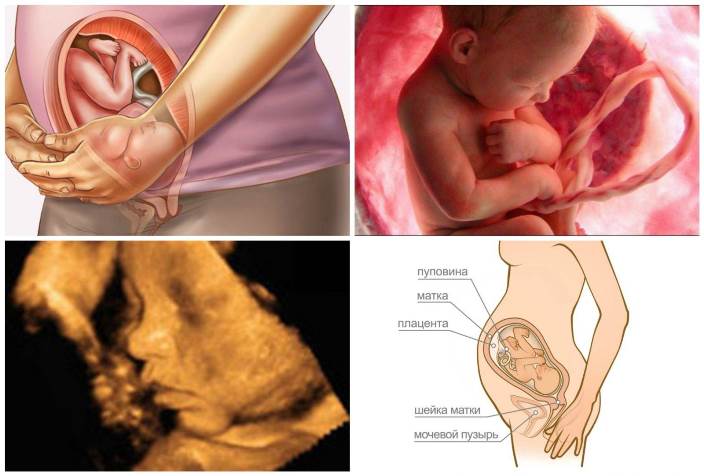

На этом сроке можно быть уверенной в том, что ребенок уже сформирован, и его внутренние органы готовы к встрече с внешним миром. Также стоит отметить, что все системы функционируют на должном уровне. Единственное, о чем стоит беспокоиться, так это о неполноценности легких.

Первичная смазка, которая была на ребенке, постепенно уходит, а ведь именно она на протяжении долгих весьма месяцев защищала малыша от воздействия патогенных бактерий и различных вредоносных микроорганизмов. Период беременности в 36 недель сопряжен с различными положительными моментами:

- В ходе ультразвукового исследования видны контуры всех органов и конечностей;

Вес плода существенно увеличился, и уже по нему можно судить, насколько полноценным было внутриутробное развитие. Нередко женщины ощущают повышенный тонус матки в 36 недель беременности. Это обусловлено тем, что находясь в утробе, все также происходит набор веса, поскольку он активно подготавливается к появлению на свет. Такое состояние диагностируется у 85% женщин.

Этот срок показывает, что ребенок уже полностью готов к встрече с миром, поскольку все органы и системы работают нормально и без сбоев. В 36 недель только легкие малыша не готовы к расставанию с мамой, однако и они уже практически сформировались.

Малыш начинает постепенно терять первородную смазку, которой он был покрыт с самого начала своего формирования. Именно она защищала его долгие 8 месяцев от бактерий и прочих вредных микроорганизмов.

Масса тела малыша дает понять, что каждая неделя его развития принесла ему значительную пользу – все органы и кости ребенка увеличились, в результате чего он стал похож по внешности и строению организма на взрослого человека.

- УЗИ. Напряжение мускулатуры задней стенки органа свидетельствует о нарушении процесса вынашивания, а если передняя часть тоньше, чем задняя — это может указывать на неправильное развитие плода.